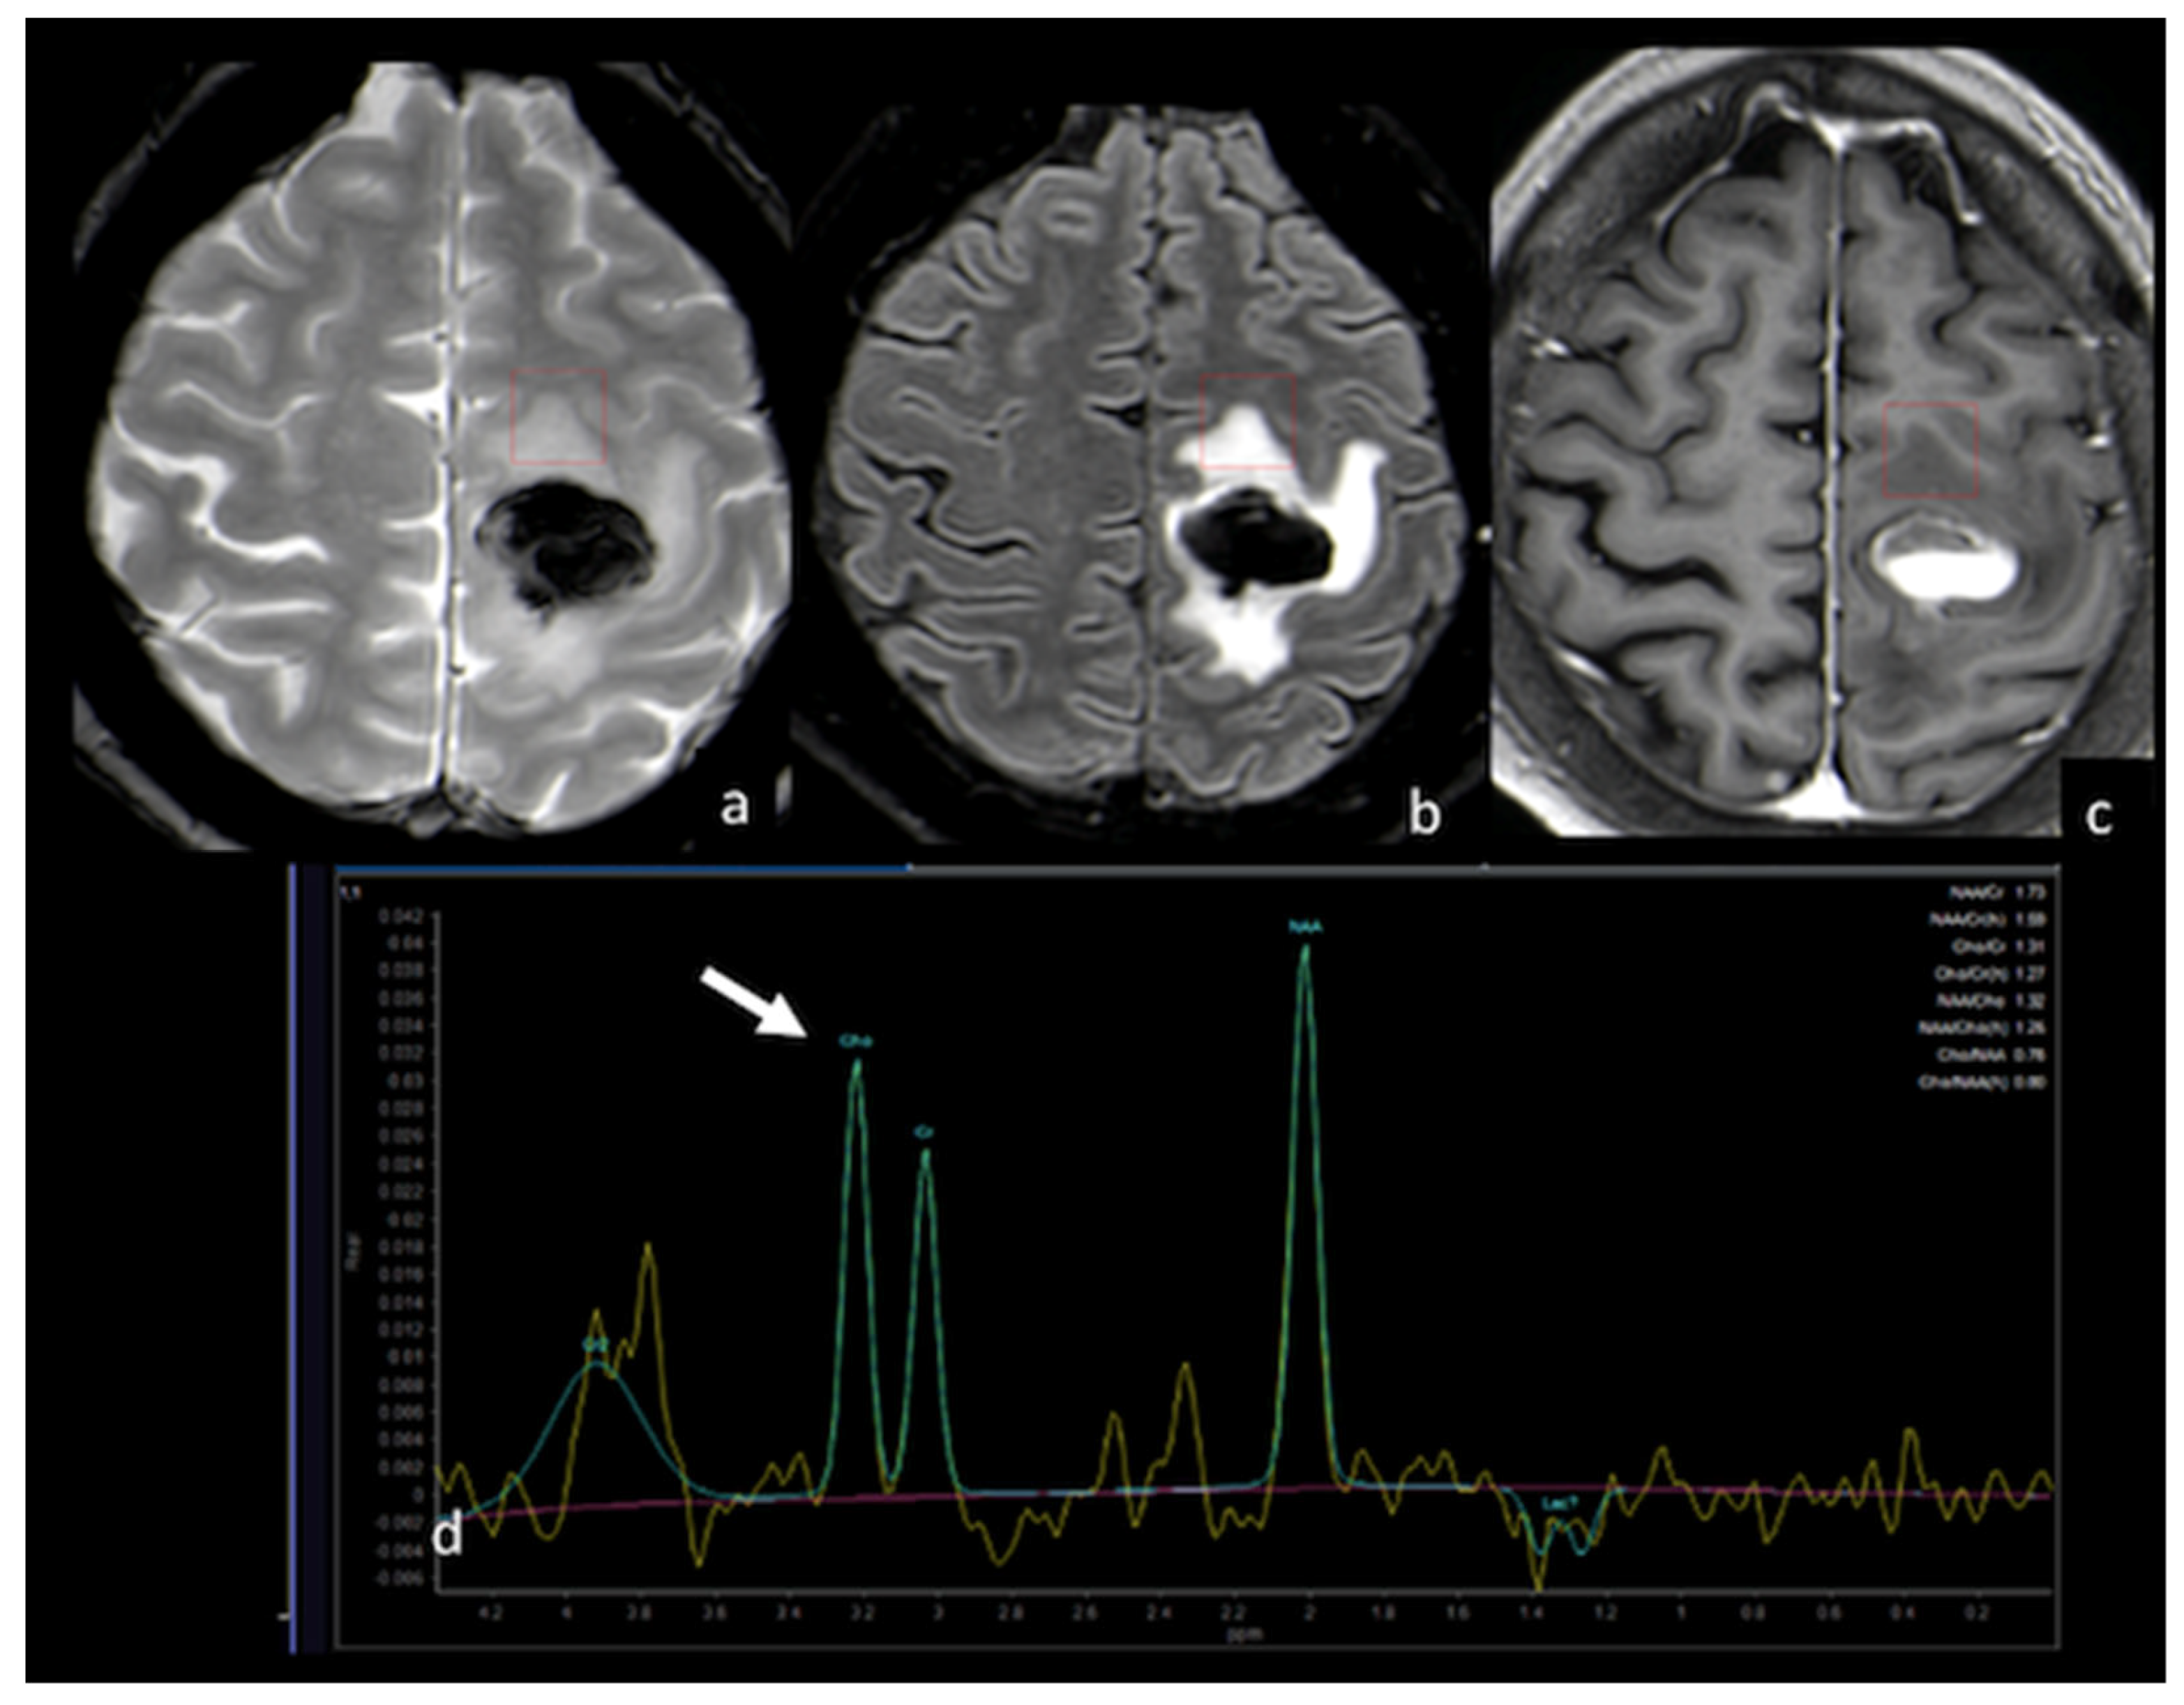

- Chiang, I.C.; Kuo, Y.T.; Lu, C.Y.; Yeung, K.W.; Lin, W.C.; Sheu, F.O.; Liu, G.C. Distinction between high-grade gliomas and solitary metastases using peritumoral 3-T magnetic resonance spectroscopy, diffusion, and perfusion imagings. Neuroradiology 2004, 46, 619–627. [Google Scholar] [CrossRef] [PubMed]

- Wijnen, J.P.; Idema, A.J.; Stawicki, M.; Lagemaat, M.W.; Wesseling, P.; Wright, A.J.; Scheenen, T.W.; Heerschap, A. Quantitative short echo time 1H MRSI of the peripheral edematous region of human brain tumors in the differentiation between glioblastoma, metastasis, and meningioma. J. Magn. Reson. Imaging 2012, 36, 1072–1082. [Google Scholar] [CrossRef] [PubMed]

- Ricci, R.; Bacci, A.; Tugnoli, V.; Battaglia, S.; Maffei, M.; Agati, R.; Leonardi, M. Metabolic findings on 3T 1H-MR spectroscopy in peritumoral brain edema. AJNR Am. J. Neuroradiol. 2007, 28, 1287–1291. [Google Scholar] [CrossRef]